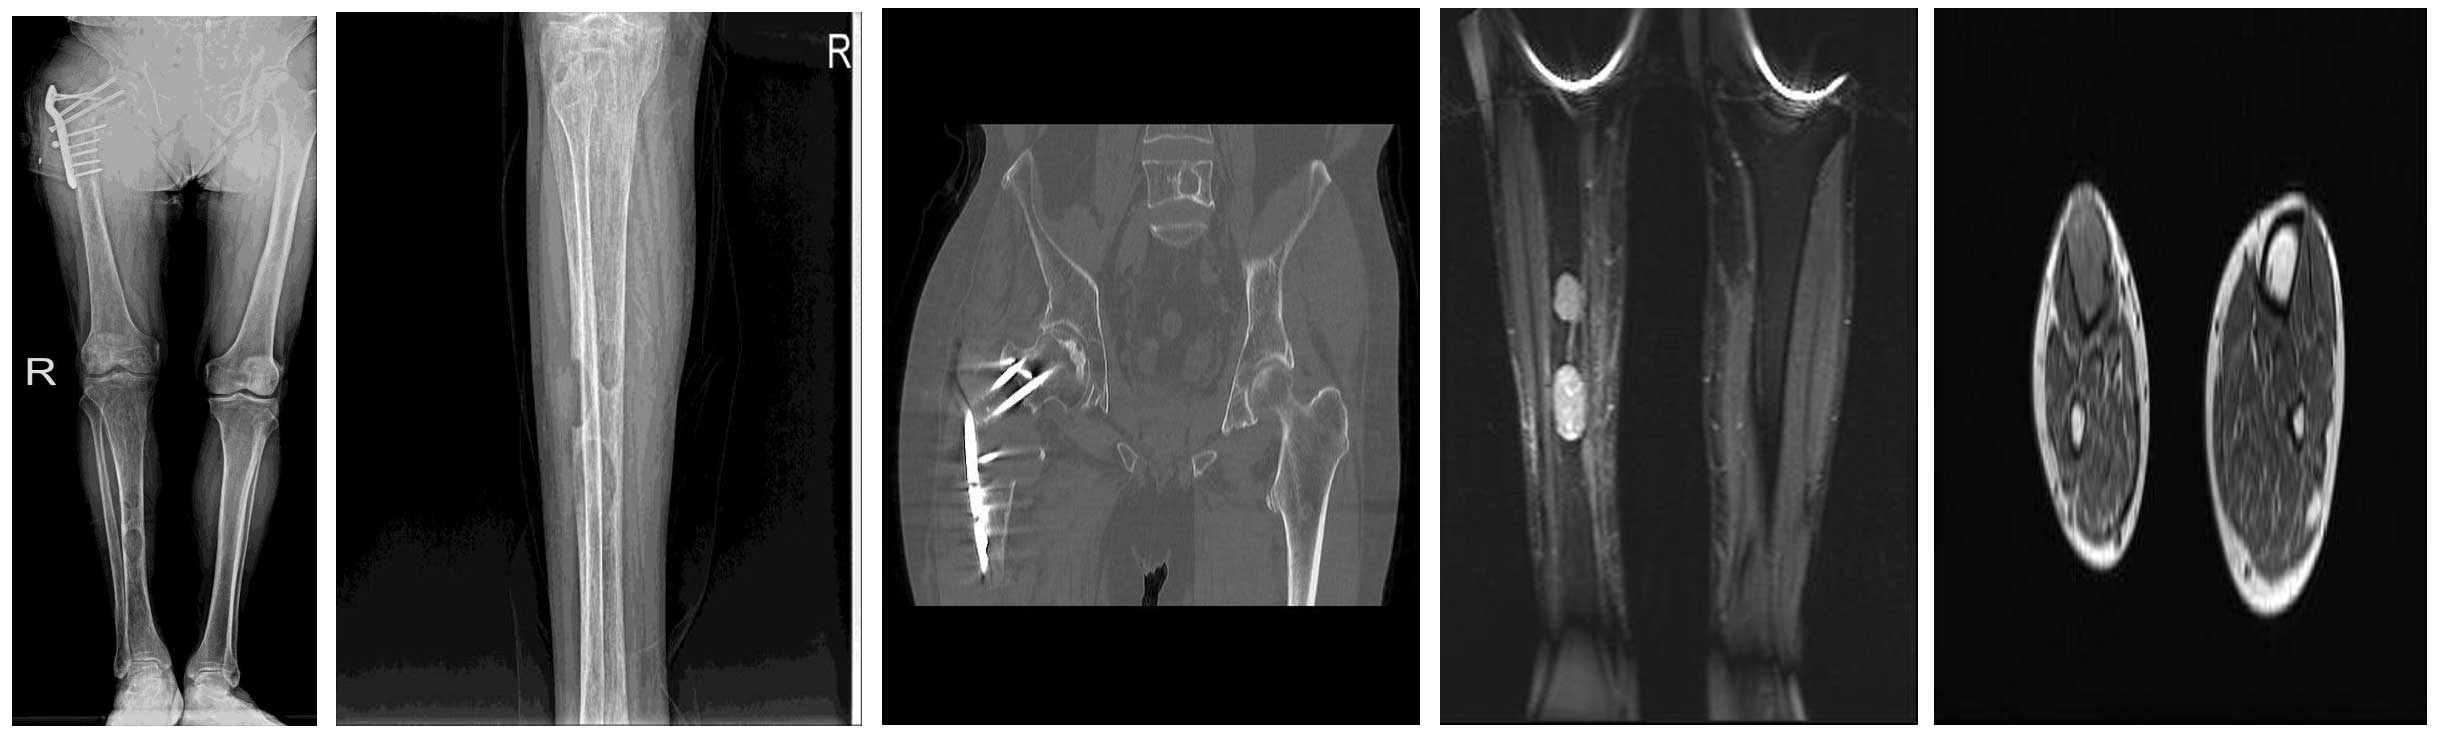

Ameliyat Öncesi: Röntgende sağ proksimal femurda materyal yetmezliği, Tomografide sağ proksimal femurda nüks, MR’da sağ tibiada iki yerde metastaz odağı görülmekte.